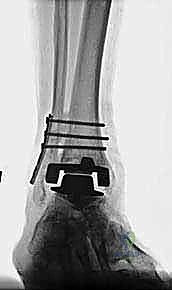

مراجعة مفصل الكاحل الصناعي هي إجراء جراحي ضروري لمعالجة المشاكل التي قد تنشأ بعد الجراحة الأولية، مثل كسور الكعبين أو عدم استقرار المفصل. يتضمن العلاج التشخيص الدقيق عبر الأشعة السينية والتصوير المقطعي، يليه التدخل الجراحي لتثبيت الكسور واستعادة وظيفة الكاحل، مع التركيز على التعافي المبكر.

تُعد جراحة مراجعة مفصل الكاحل الصناعي (Revision Total Ankle Replacement) من الإجراءات الجراحية المتقدمة والبالغة الدقة في عالم جراحة العظام الحديثة. لا تقتصر هذه الجراحة على مجرد استبدال مفصل تالف بآخر جديد، بل هي عملية إنقاذ معقدة للغاية تهدف إلى معالجة المشاكل الميكانيكية والبيولوجية التي تنشأ بعد الجراحة الأولية. من أبرز هذه المشاكل: الفشل الميكانيكي للمفصل، تحلل العظام (Osteolysis)، أو حدوث كسور معقدة في الكعبين (Malleolar Fractures) المحيطة بالمفصل الصناعي. يتطلب هذا الإجراء تقييماً سريرياً وشعاعياً دقيقاً يشمل التصوير المقطعي ثلاثي الأبعاد والأشعة السينية، يليه تدخل جراحي دقيق لاستعادة التوازن الحيوي والميكانيكي للكاحل والحفاظ على الطرف من البتر أو الدمج.

- الأشعة السينية مع تحميل الوزن (Weight-bearing X-rays): لتقييم الزوايا الميكانيكية وتحديد مدى هبوط المفصل أو وجود كسور في الكعب.

* دمج الكاحل (Ankle Arthrodesis): إذا كان التآكل العظمي هائلاً ولا يسمح بتركيب مفصل جديد، يتم إزالة المفصل الصناعي ودمج عظمة الساق مع عظمة الكاحل باستخدام مسامير وصفائح معدنية وطعوم عظمية.

يتم إدخال المفصل الجديد المخصص للمراجعة، والذي يحتوي غالباً على سيقان (Stems) تدخل عميقاً في عظمة الساق وعظمة الكاحل لضمان الثبات الميكانيكي. في حال وجود كسور في الكعب، يتم تثبيتها في هذه المرحلة.